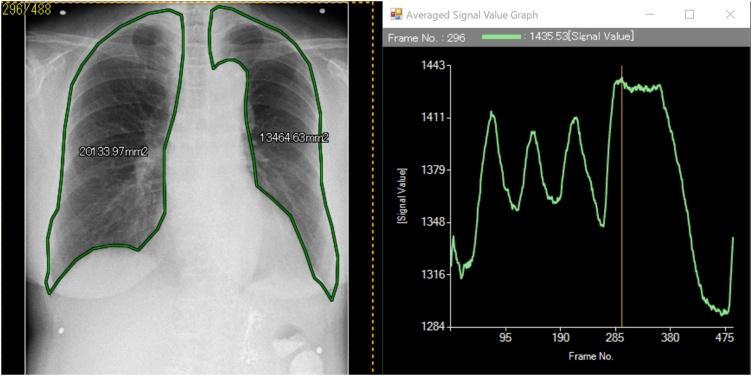

Projected lung areas using dynamic X-ray (DXR).

One hundred sixty-two healthy volunteers who received medical check-ups for health screening were included in this study. All subjects underwent DXR in both posteroanterior (PA) and lateral views and pulmonary function tests on the same day. All the volunteers took several tidal breaths before one forced breath as instructed. The outlines of lungs were contoured manually on the workstation with reference to the motion of diaphragm and the graph of pixel values. The PLAs were calculated automatically, and correlations with pulmonary functions and demographic data were analyzed statistically.

RESULTS

The PLAs have correlation with physical characteristics, including height, weight and BMI, and pulmonary functions such as vital capacity (VC) and forced expiratory volume in one second (FEV). VC and FEV revealed moderate correlation with the PLAs of PA view in forced inspiratory phase (VC: right, r = 0.65; left, r = 0.69. FEV1: right, r = 0.54; left, r = 0.59). Multivariate analysis showed that body mass index (BMI), sex and VC were considered independent correlation factors, respectively.